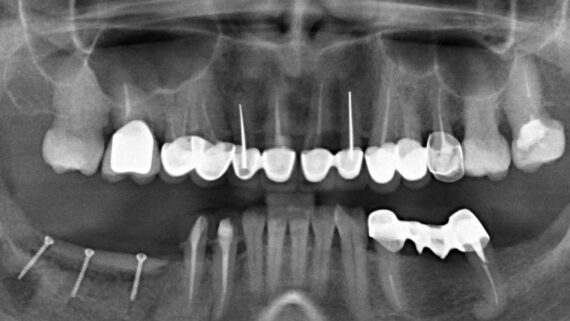

1. Стадия воспалительного процесса. За редким исключением большинство зубов удаляются из-за развитого воспалительного процесса (периодонтита) и невозможности его терапевтического лечения и/или реставрации зуба цивилизованными методами. Ремиссия или хроническое течение заболевания говорит о том, что организм «справляется» с воспалительным очагом – и с этой точки зрения, наличие даже обширного периапикального процесса не является противопоказанием к установке импланта в лунку зуба. И наоборот, обострение периодонтита, болевой синдром, гноетечение и т. п. является противопоказанием к немедленной имплантации.

Это, разумеется, относительно, потому степень риска оценивается в каждом конкретном клиническом случае (рис. 1-4):

Другими словами, до определенных пределов (каких – рассматривается индивидуально) даже острый воспалительный процесс не является абсолютным противопоказанием для операции немедленной имплантации.